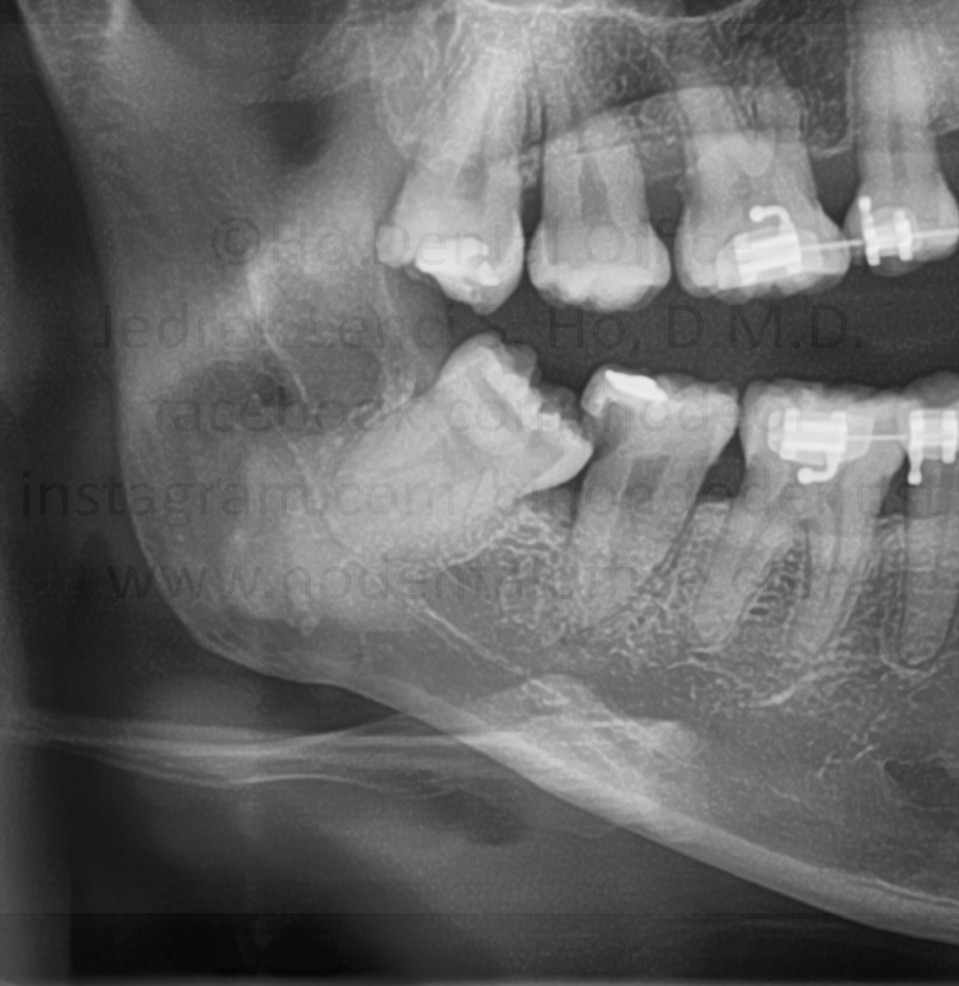

- prevention of periodontal disease - Periodontal pockets may develop from frequent food impaction. This may lead to further gingival attachment loosening ("flabby gums") which will again lead to more food impaction. As periodontal disease progress, it will eventually erode healthy bone and loosen tooth.

![]() |